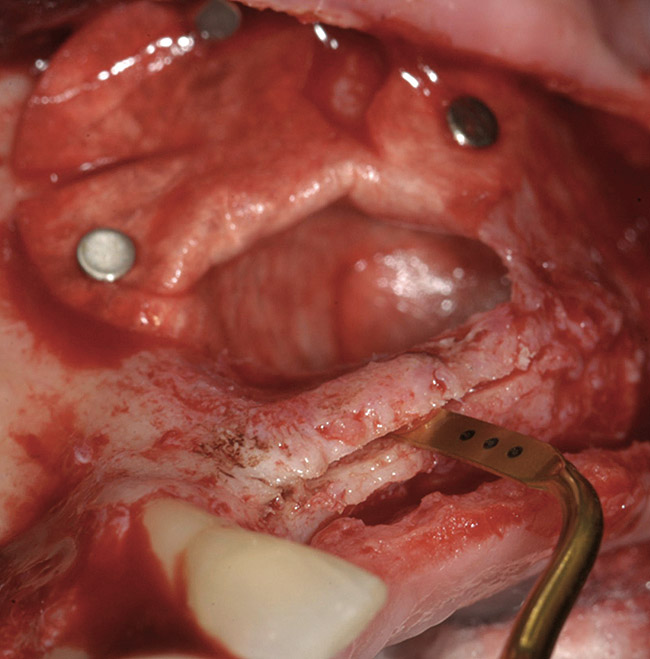

A 62-year-old woman was referred for fixed tooth replacement of the missing maxillary left cuspid, bicuspids, and first molar (Figure 11). Clinical and CBCT evaluation revealed an almost fully pneumatized maxillary left sinus along with alveolar width deficiency. The treatment plan called for a four-unit, implant-supported splinted fixed bridge. A left sinus augmentation along with a ridge split and interpositional bone graft consisting of rhBMP-2/ACS (INFUSE Bone Graft) and mineralized allograft (MinerOss) covered by a dense porous polyethylene mesh (Medpor®, Stryker, www.stryker.com) were done simultaneously (Figure 12, Figure 13 and Figure 14). Six months later, a follow-up CBCT revealed a well-incorporated graft with adequate bone volume and density for implant placement (Figure 15 and Figure 16). Final bridge fabrication followed 3 months later (Figure 17 and Figure 18).

Figure 12  Preparation of left sinus augmentation and alveolar ridge split.

Figure 12

Figure 20  Removal of the failing implants.

Figure 20

Figure 21  Bone grafting with rhPDGF, allograft, and xenograft.

Figure 21